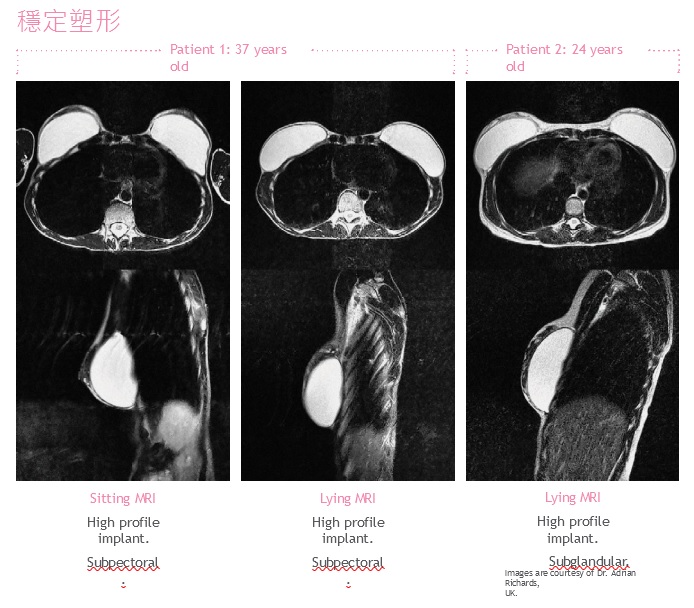

♦長鏈與短鏈有機矽聚合物的比例和交聯密度極度優化,以達到充分的凝膠流動性但同時具有高度凝聚性,因此形狀穩定。 它的柔軟性和凝聚力使外科醫生可用更小的切口,更容易植入,並有助於最大限度地減少創傷。 ♦凝膠的設計具有塑形穩定性,透過 MRI 顯示,在站立和仰臥位置能顯示自然乳房組織輪廓。 ♦100% 凝膠填充,可減少水波紋的產生。 高凝聚力| 柔軟 | 塑形穩定 | 100%填充 | 幾乎牢不可破 自然流動,增強飽滿度